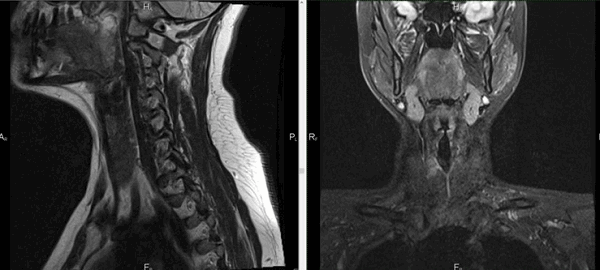

Магнитно-резонансная томография обеспечивает детальную визуализацию рыхлых структур. В результате сканирования получают послойные изображения щитовидной железы, расположенных рядом лимфатических узлов, кровеносных сосудов, мягких тканей шеи, гортани.

Исследование отличается высокой информативностью по сравнению с другими методами аппаратной диагностики. Томограммы показывают изменения формы и размеров анатомического образования, позволяют выявить структурные нарушения и патологические очаги диаметром от 3 мм.

При увеличении железы в размерах по описанию томограмм можно определить характер гиперплазии. Узелки и капсулы выглядят на снимках МРТ как очаги с гипо- или гиперинтенсивным сигналом, отличным от реакции окружающих тканей. Метод показывает сдавление трахеи новообразованием, распространение патологического процесса в загрудинное пространство.

Мягкие ткани шеи на МРТ